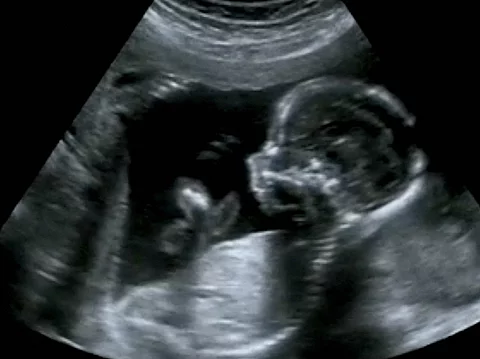

FruchtwasserembolieWas sind die Risikofaktoren?

Die Risikofaktoren für einen tödlichen Verlauf einer Fruchtwasserembolie standen im Fokus einer Studie von Wissenschaftlern um Chengya Zhu von der Zheijang-Universität in Hangzhou.